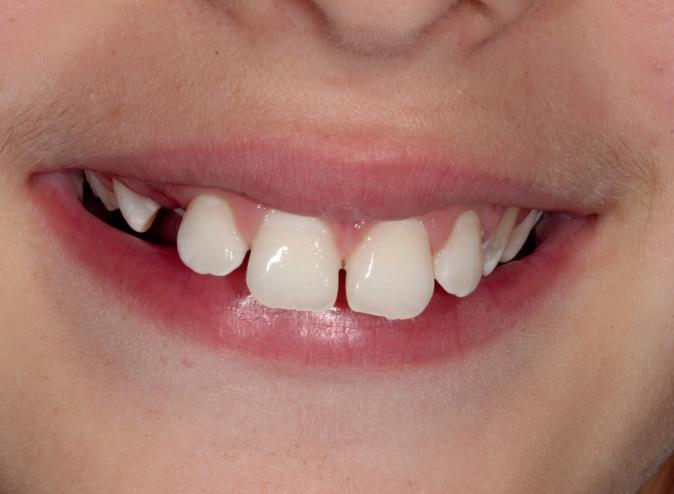

material matters

To use clear aligners to their greatest potential, it’s important to look briefly at their treatment ceiling. Complex cases that include severe bite issues, large gaps, or severe crowding may make this form of treatment less suitable, instead requiring traditional fixed braces. The literature has also cited distalisation, rotation and extrusion as some of the more difficult movements to carry out successfully with clear aligners, and whilst it is not impossible to achieve these results, a relevant case may prompt the need for an alternative treatment approach.

However, recent developments in the materials used to create clear aligners as well as clinical approaches have improved predictability in a wider range of cases.

Polyethylene terephthalate glycol (PETG) materials have been the solution of choice for many complex designs due to their durability, high impact strength and resistance to chemical changes. With impressive mechanical and optical properties, it’s easy to see why they are increasingly preferred.

The future of complex clear aligner cases could lie in shape memory polymers (SMPs), sometimes known as actively moving polymers. This material offers the ability to revert to an original shape when achieving a necessary transitionary trigger, such as a certain temperature for a designated time period. During a treatment cycle, the SMP-based aligner could be subjected to such a trigger, reverting to a predefined shape, and in turn generating forces which can produce orthodontic tooth movement. When designed to harbour multiple aligner shapes within its form, it could reduce the number of aligners used during orthodontic treatment and achieve complex corrections sooner.

Step by step

When tackling a complex case suitable for aligner therapy, treatment is most effective when the dentist creates an efficient and actionable treatment plan. Therefore, one of the most important skills for a clinician providing clear aligners for complex cases is an understanding of how to implement staging.

Those that have prior experience in orthodontics may know that staging refers to the breakdown of an intended movement of teeth in a sequential manner, with the use of aligners. This segmented approach

allows for the close control over linear and rotational movements over time, with each new aligner achieving a specific step that gets a patient closer to their end goal. In complex cases, staging orthodontic tooth movement is essential and can be used to attain better treatment outcomes.

When used in the treatment of severe crowding, staging has provided no significant differences in results when compared to fixed brace treatments, including in case duration. One 2022 study broke up the process into three overarching stages of ‘decrowding‘, ‘space closure’ and ‘fine-tuning’. This allows for targeted movement of the crowded anterior teeth, before achieving a class I canine and molar relationship, and making final adjustments, such as overcorrections – recommended by many in case of possible relapses – and closures of any residual spaces.